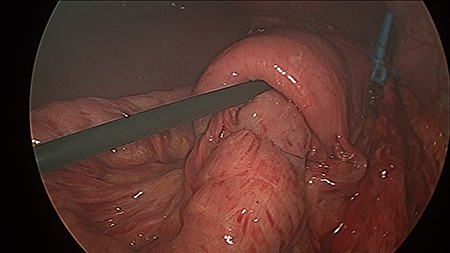

The patient was positioned supine, and cut down entry periumbilically was performed with a 10-mm camera port and two 5-mm working ports inserted. On laparoscopy, a retrograde intussusception with the intussuscipien constituted the gastric pouch and the intussusceptum constituting the alimentary limb of the jejunum was identified. Just distal to the intussusceptum, there was a jejunal mesenteric defect, with demonstrable thinning of mesenteric fat and various tears. Through this defect, the remnant stomach, normally situated on the left side of the gastric pouch, was found to have herniated from the left to right through this jejunal mesenteric defect, posterior to the alimentary limb in the supracolic compartment. This internal hernia was reversed and the defect closed with non-dissolvable V-Loc™ barbed sutures. A slipped MiniMizer gastric ring was then identified 3 cm distal to the gastrojejunal anastomosis (Fig. 2). No fixation sutures were identified. On release of the ring, 25 cm of alimentary limb jejunum was, with gentle traction, pulled from its invagination into the gastric pouch through where the ring was originally placed (Fig. 3). Surprisingly, all bowel was viable and no resection was required.

The MiniMizer ring has been removed. Alimentary limb jejunal intussusception and left to right remnant stomach herniation can be appreciated. Gentle traction on the intussusceptum resulted in 25 cm of viable bowel pulled from the invagination.